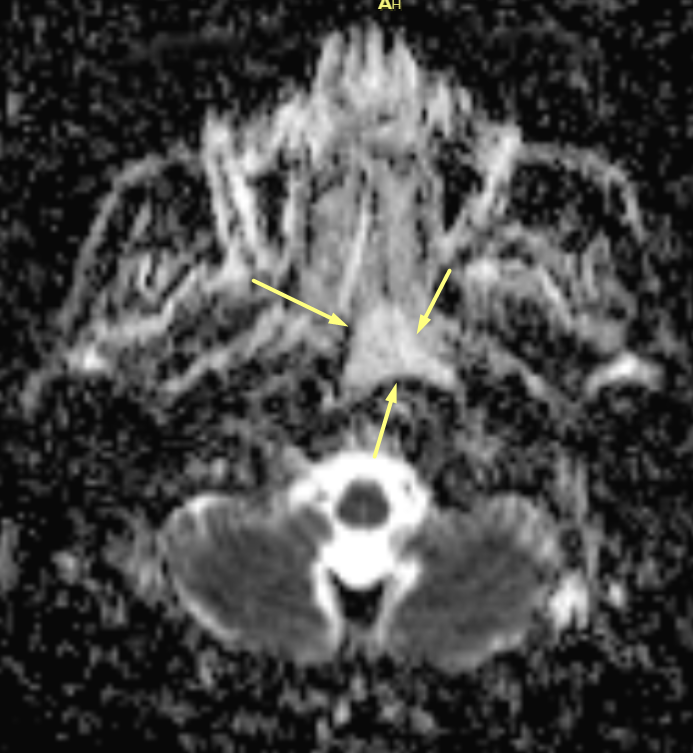

Ve lezyon diffüzyon kısıtlaması göstermiyordu.

DWI ADC

2️Difüzyon

Restriksiyon yok

➡ Solid malign lezyon olasılığı çok düşer

✔ DWI negatif